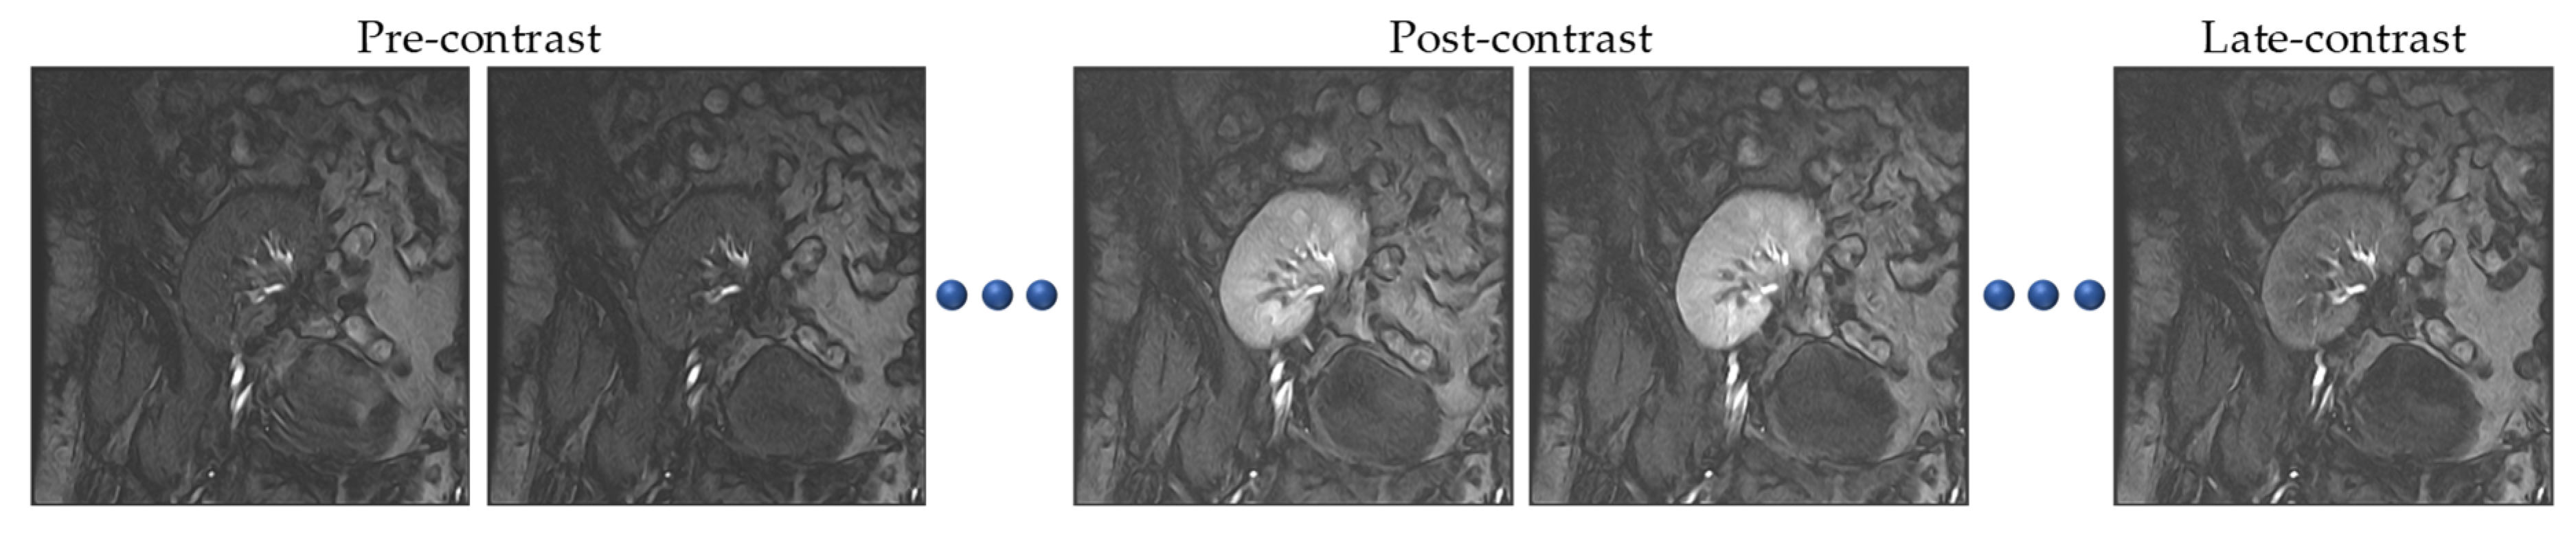

2.1. Data